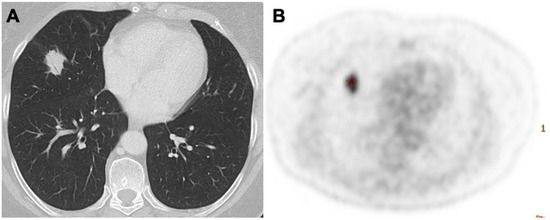

3.2. Nodules and Masses

- Albano, D.; Borghesi, A.; Bosio, G.; Bertoli, M.; Maroldi, R.; Giubbini, R.; Bertagna, F. Pulmonary mucosa-associated lymphoid tissue lymphoma: F-FDG PET/CT and CT findings in 28 patients. Br. J. Radiol. 2017, 90, 20170311. [Google Scholar] [CrossRef]

- Deng, W.; Wan, Y.; Yu, J.Q. Pulmonary MALT Lymphoma has variable features on CT. Sci. Rep. 2019, 9, 8657. [Google Scholar] [CrossRef]

- Cozzi, D.; Dini, C.; Mungai, F.; Puccini, B.; Rigacci, L.; Miele, V. Primary pulmonary lymphoma: Imaging findings in 30 cases. Radiol. Med. 2019, 124, 1262–1269. [Google Scholar] [CrossRef]

- Bligh, M.P.; Borgaonkar, J.N.; Burrell, S.C.; MacDonald, D.A.; Manos, D. Spectrum of CT findings in thoracic extranodal non-Hodgkin lymphoma. Radiographics 2017, 37, 439–461. [Google Scholar] [CrossRef]

- Diederich, S.; Link, T.; Zühlsdorf, H.; Steinmeyer, E.; Wormanns, D.; Heindel, W. Pulmonary manifestations of Hodgkin’s disease: Radiographic and CT findings. Eur. Radiol. 2001, 11, 2295–2305. [Google Scholar] [CrossRef]

- Angirish, B.; Sanghavi, P.; Jankharia, B. Pulmonary manifestations of lymphoma: A pictorial essay. Lung India 2020, 37, 263–267. [Google Scholar] [CrossRef] [PubMed]

- Lewis, E.R.; Caskey, C.I.; Fishman, E.K. Lymphoma of the lung: CT findings in 31 patients. AJR Am. J. Roentgenol. 1991, 156, 711–714. [Google Scholar] [CrossRef]